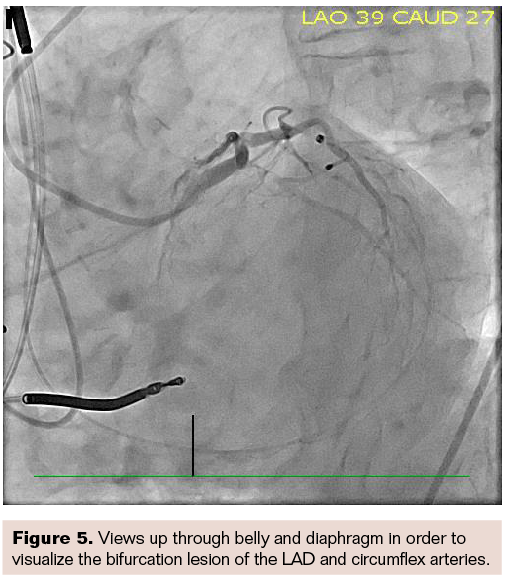

Figure 5 is again the same patient and same angulation, but a steep left anterior oblique (LAO) caudal view. We were imaging up through the belly and the diaphragm, and in spite of that, were still able to get a very clear, acceptable image in order to target a bifurcation lesion between the left anterior descending (LAD) and circumflex arteries. In order to land the stent precisely, we needed to be able to visualize the bifurcation very clearly, and this was the only view where we could separate out the bifurcation of the LAD and circumflex. These are steep, angulated views in an obese patient, but ARTIS icono provides a nice, clear image.